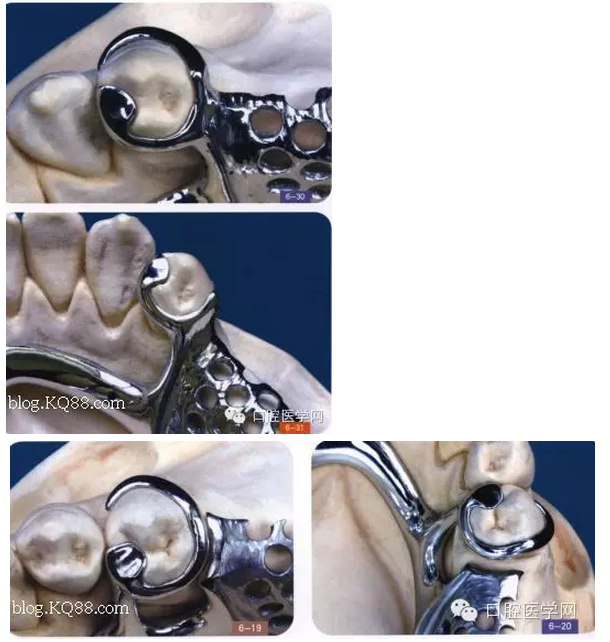

其實(shí)RPI,RPA卡換組對于后牙游離缺失在臨床中很常用,CPI卡換組由三部分組成,近中和支托,遠(yuǎn)中臨面板,和頰側(cè)I桿組成,近中和支托起一個應(yīng)力中斷作用,能有效預(yù)防近中基牙扭轉(zhuǎn)

1是近中合支托,2是臨面板,3是I桿

CPI卡環(huán)應(yīng)用于遠(yuǎn)中游離缺失,近中基牙不健康的基牙,當(dāng)遠(yuǎn)中產(chǎn)生一個向黏膜處的壓力時,把力量通過近中和支托,傳寄給基牙,而不是直接在遠(yuǎn)中處直接傳給給基牙,這樣就產(chǎn)生了一個應(yīng)力中斷作用能有效保護(hù)基牙,同時頰側(cè)和遠(yuǎn)中的I桿和臨面板下沉,滑動,能有效預(yù)防基牙扭轉(zhuǎn),同時I型卡環(huán)與基牙的接觸面積比較小能防止食物存留預(yù)防繼發(fā)齲但是有一前提:游離缺失處,牙槽脊條件比較好,對于牙槽脊條件差者,要設(shè)計(jì)遠(yuǎn)中合支托,如果頰側(cè)牙體倒凹大,口腔前庭小于5mm者要設(shè)計(jì)CPA卡換組(以下圖片來自中醫(yī)大)

(CPA及變異CPA卡環(huán)組)